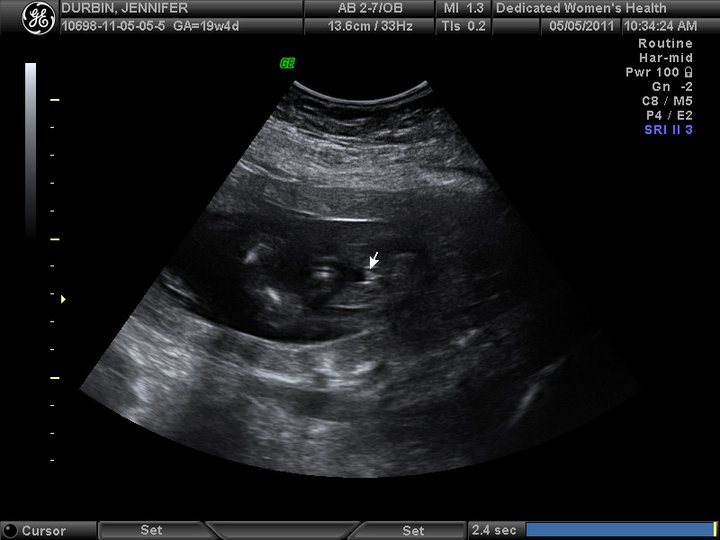

When we went to the doctors office for our ultrasound I have never been more nervous.. not even when I was PG with Matthew. She measured every possible thing she could before asking us what WE thought it was a few times during the session my heart jumped into my throat thinking it was a boy but then when she paused the machine I KNEW!! Right there in black and white were little girl parts. I was over the moon. Paull... Paull was so nervous. It was pretty funny.